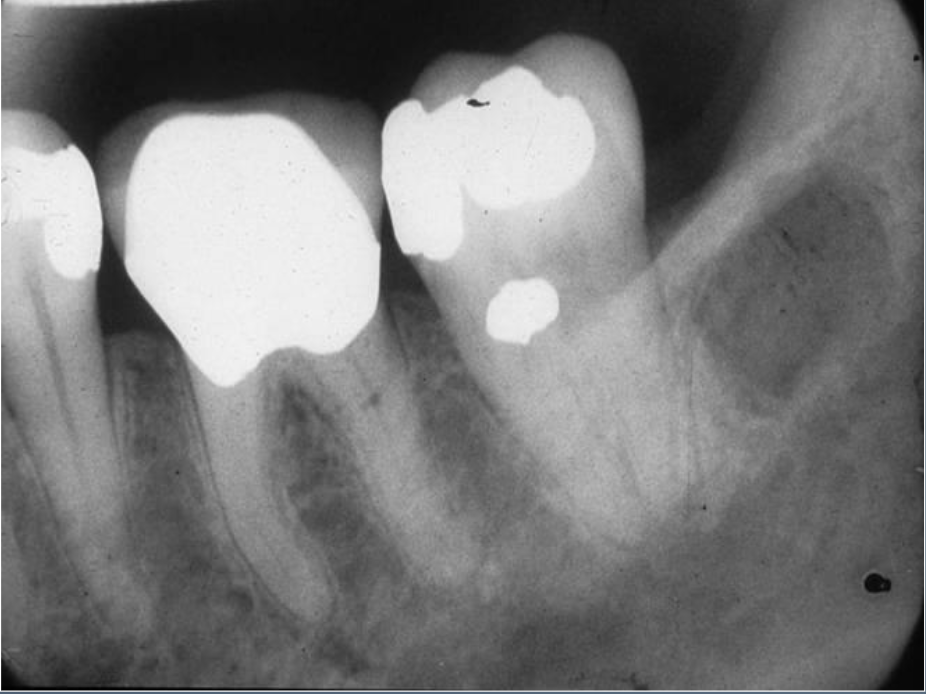

Q

What’s this?

A

CONDENSING OSTEITIS

CHRONIC FOCAL SCLEROSING OSTEOMYELITIS